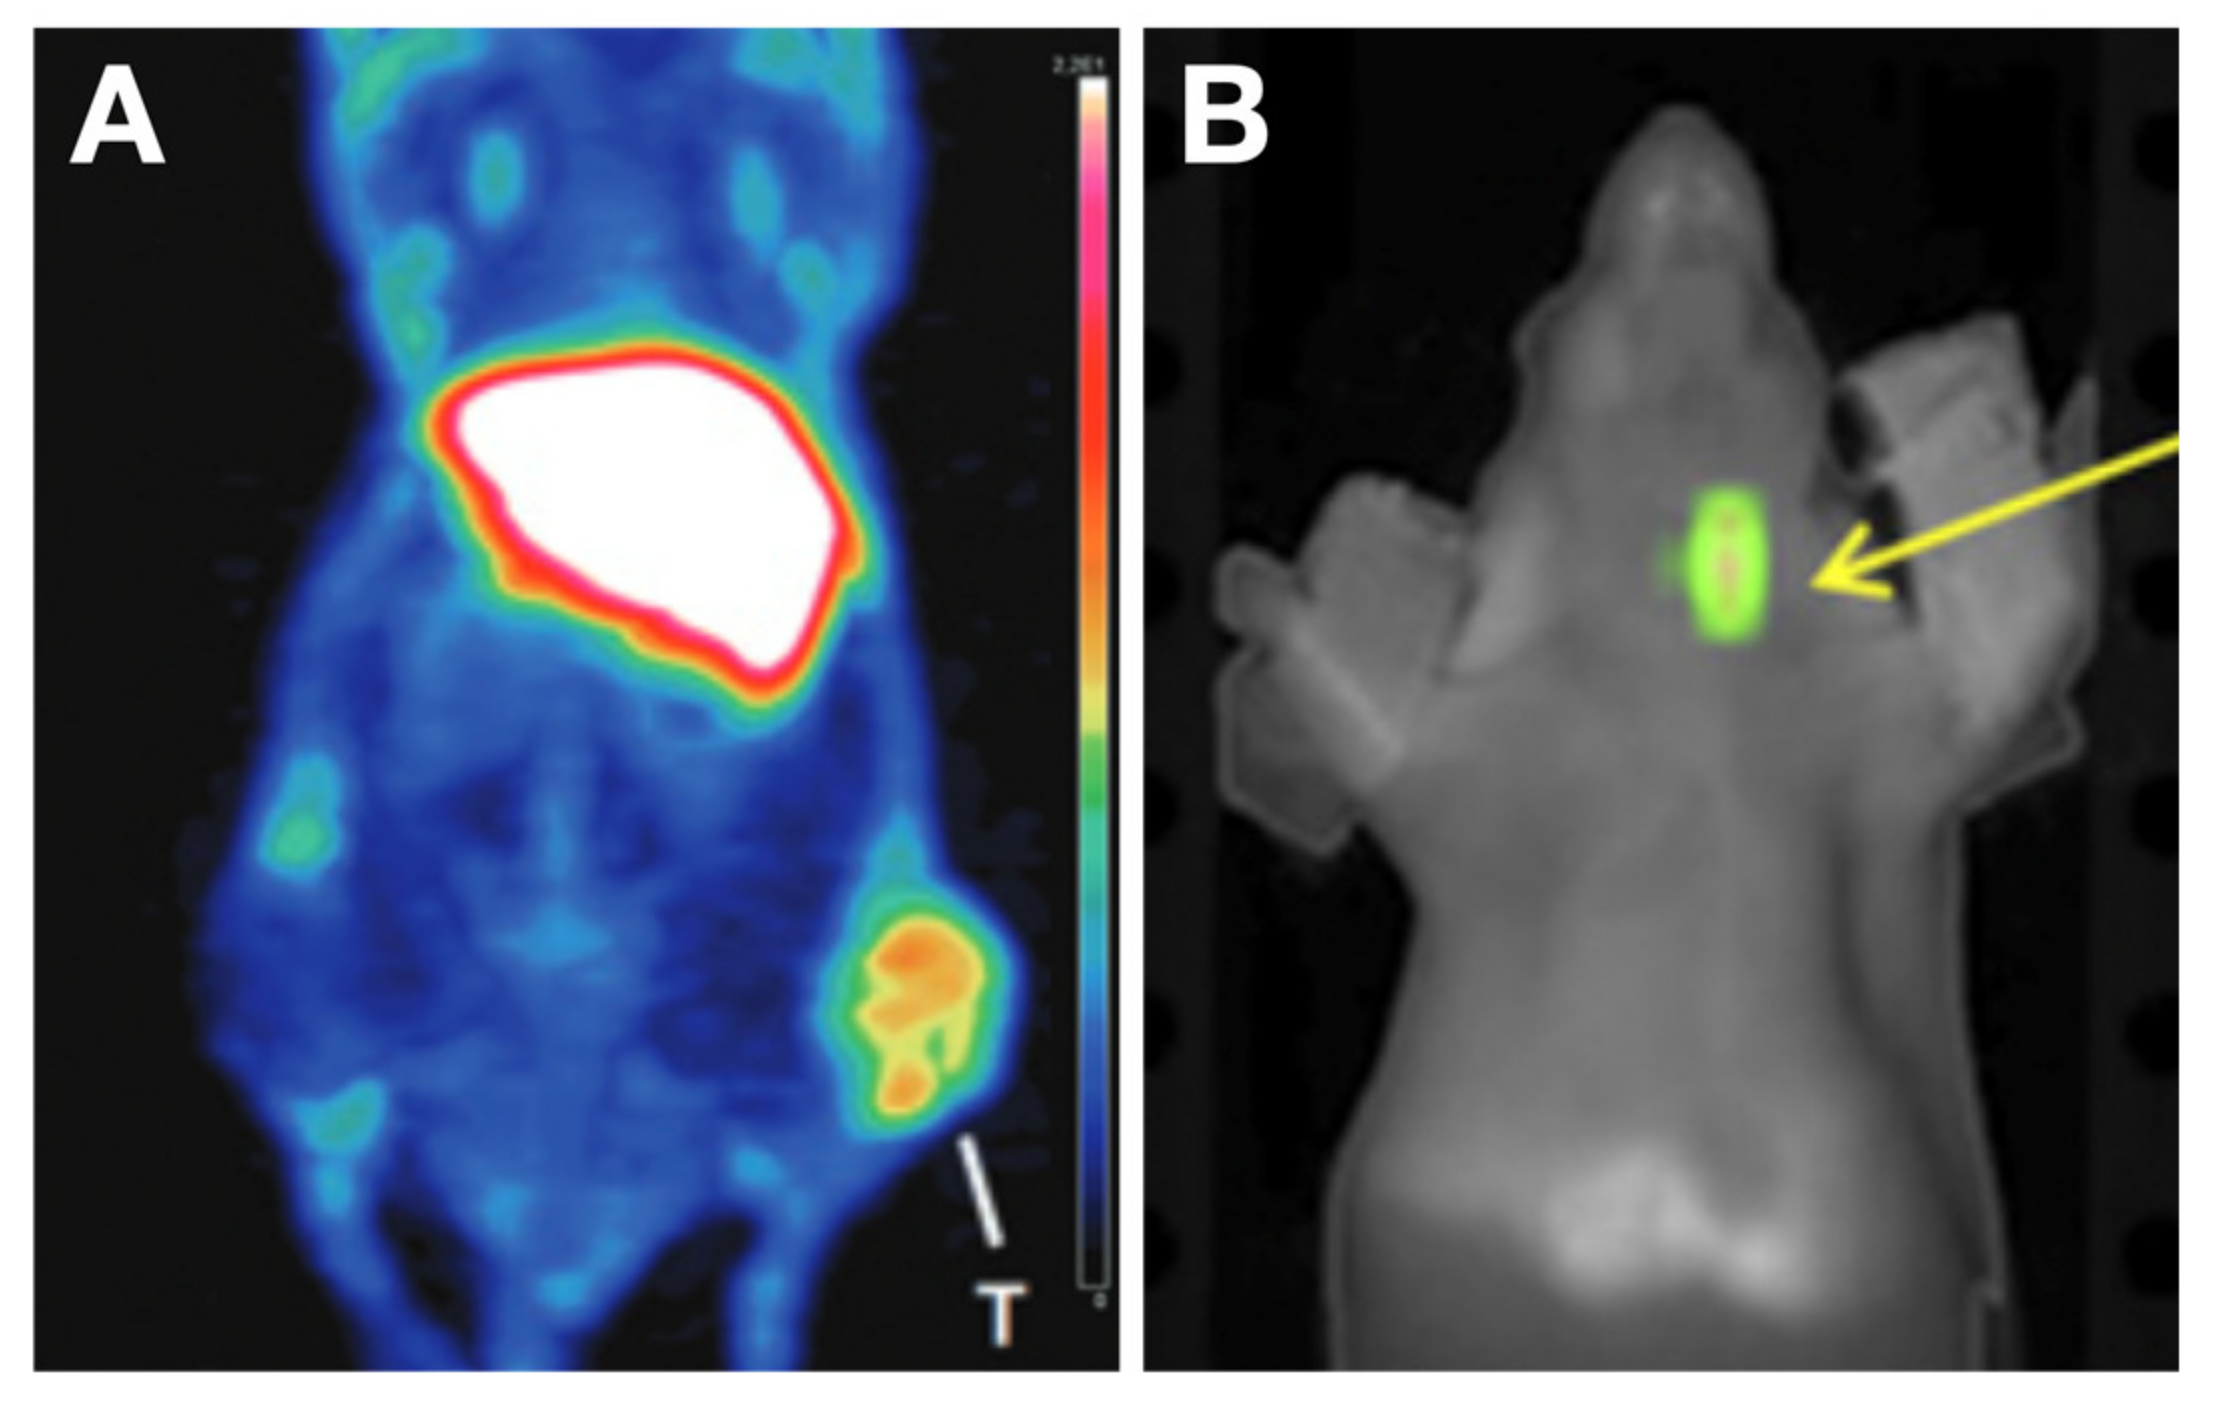

- Singh, T.D.; Song, J.; Kim, J.; Chin, J.; Ji, H.D.; Lee, J.-E.; Lee, S.B.; Yoon, H.; Yu, J.H.; Kim, S.K.; et al. A Novel Orally Active Inverse Agonist of Estrogen-Related Receptor Gamma (ERRγ), DN200434, A Booster of NIS in Anaplastic Thyroid Cancer. Clin. Cancer Res. 2019, 25, 5069–5081. [Google Scholar] [CrossRef]

- Wei, W.; Jiang, D.; Rosenkrans, Z.T.; Barnhart, T.E.; Engle, J.W.; Luo, Q.; Cai, W. HER2-Targeted Multimodal Imaging of Anaplastic Thyroid Cancer. Am. J. Cancer Res. 2019, 9, 2413–2427. [Google Scholar]